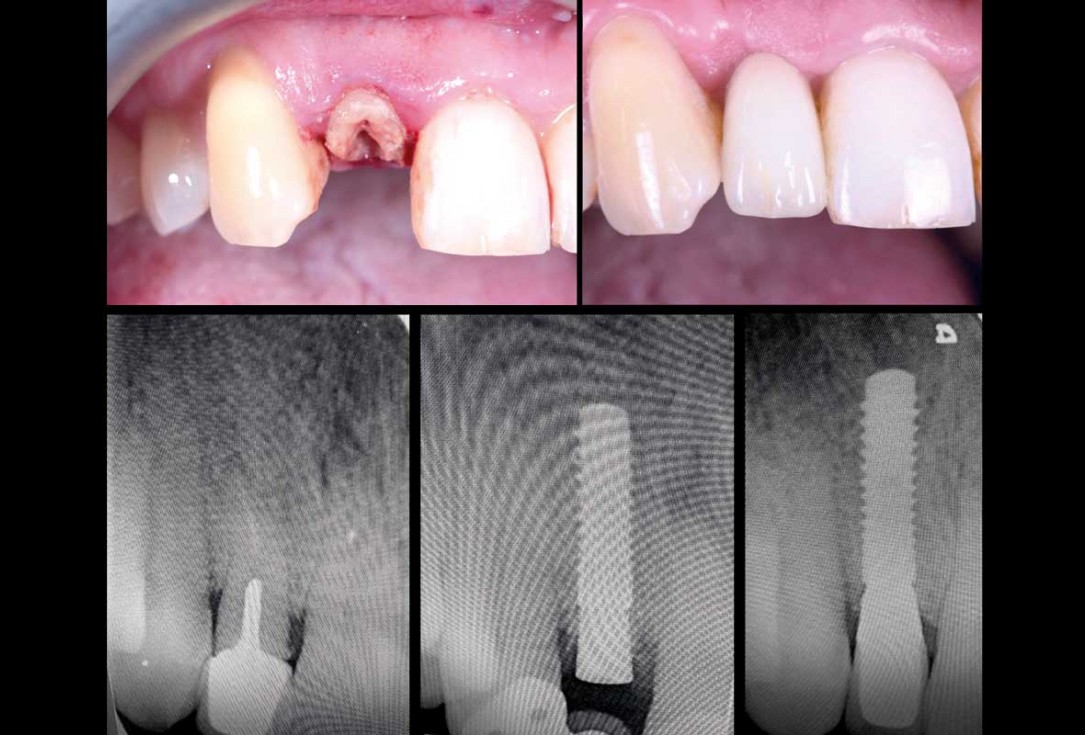

02/13 - The CBCT revealed adequate bone width and no pathology in the area, immediate implant placement was agreed

11/13 - After 10 weeks delivery of the screw retained crown with a CAD CAM milled abutment

13/13 - Before and after comparison: Clinical and radiologic view